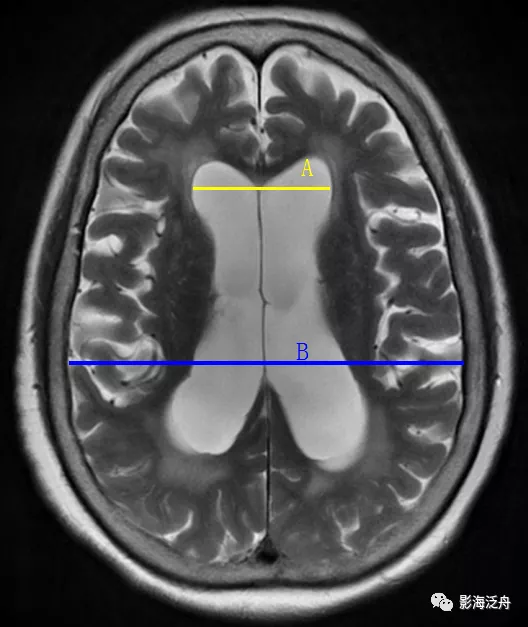

Evan指数>0.3:即两侧侧脑室前角之间的最大距离(黄线)与同层面颅腔的最大横径(蓝线)之比>0.3。

笔者认为Evan指数的可靠性有待商榷,如上图,NPH患者的Evan指数甚至还要略小于脑萎缩患者。因此,把Evan指数作为诊断NPH的必要不充分条件比较合适。